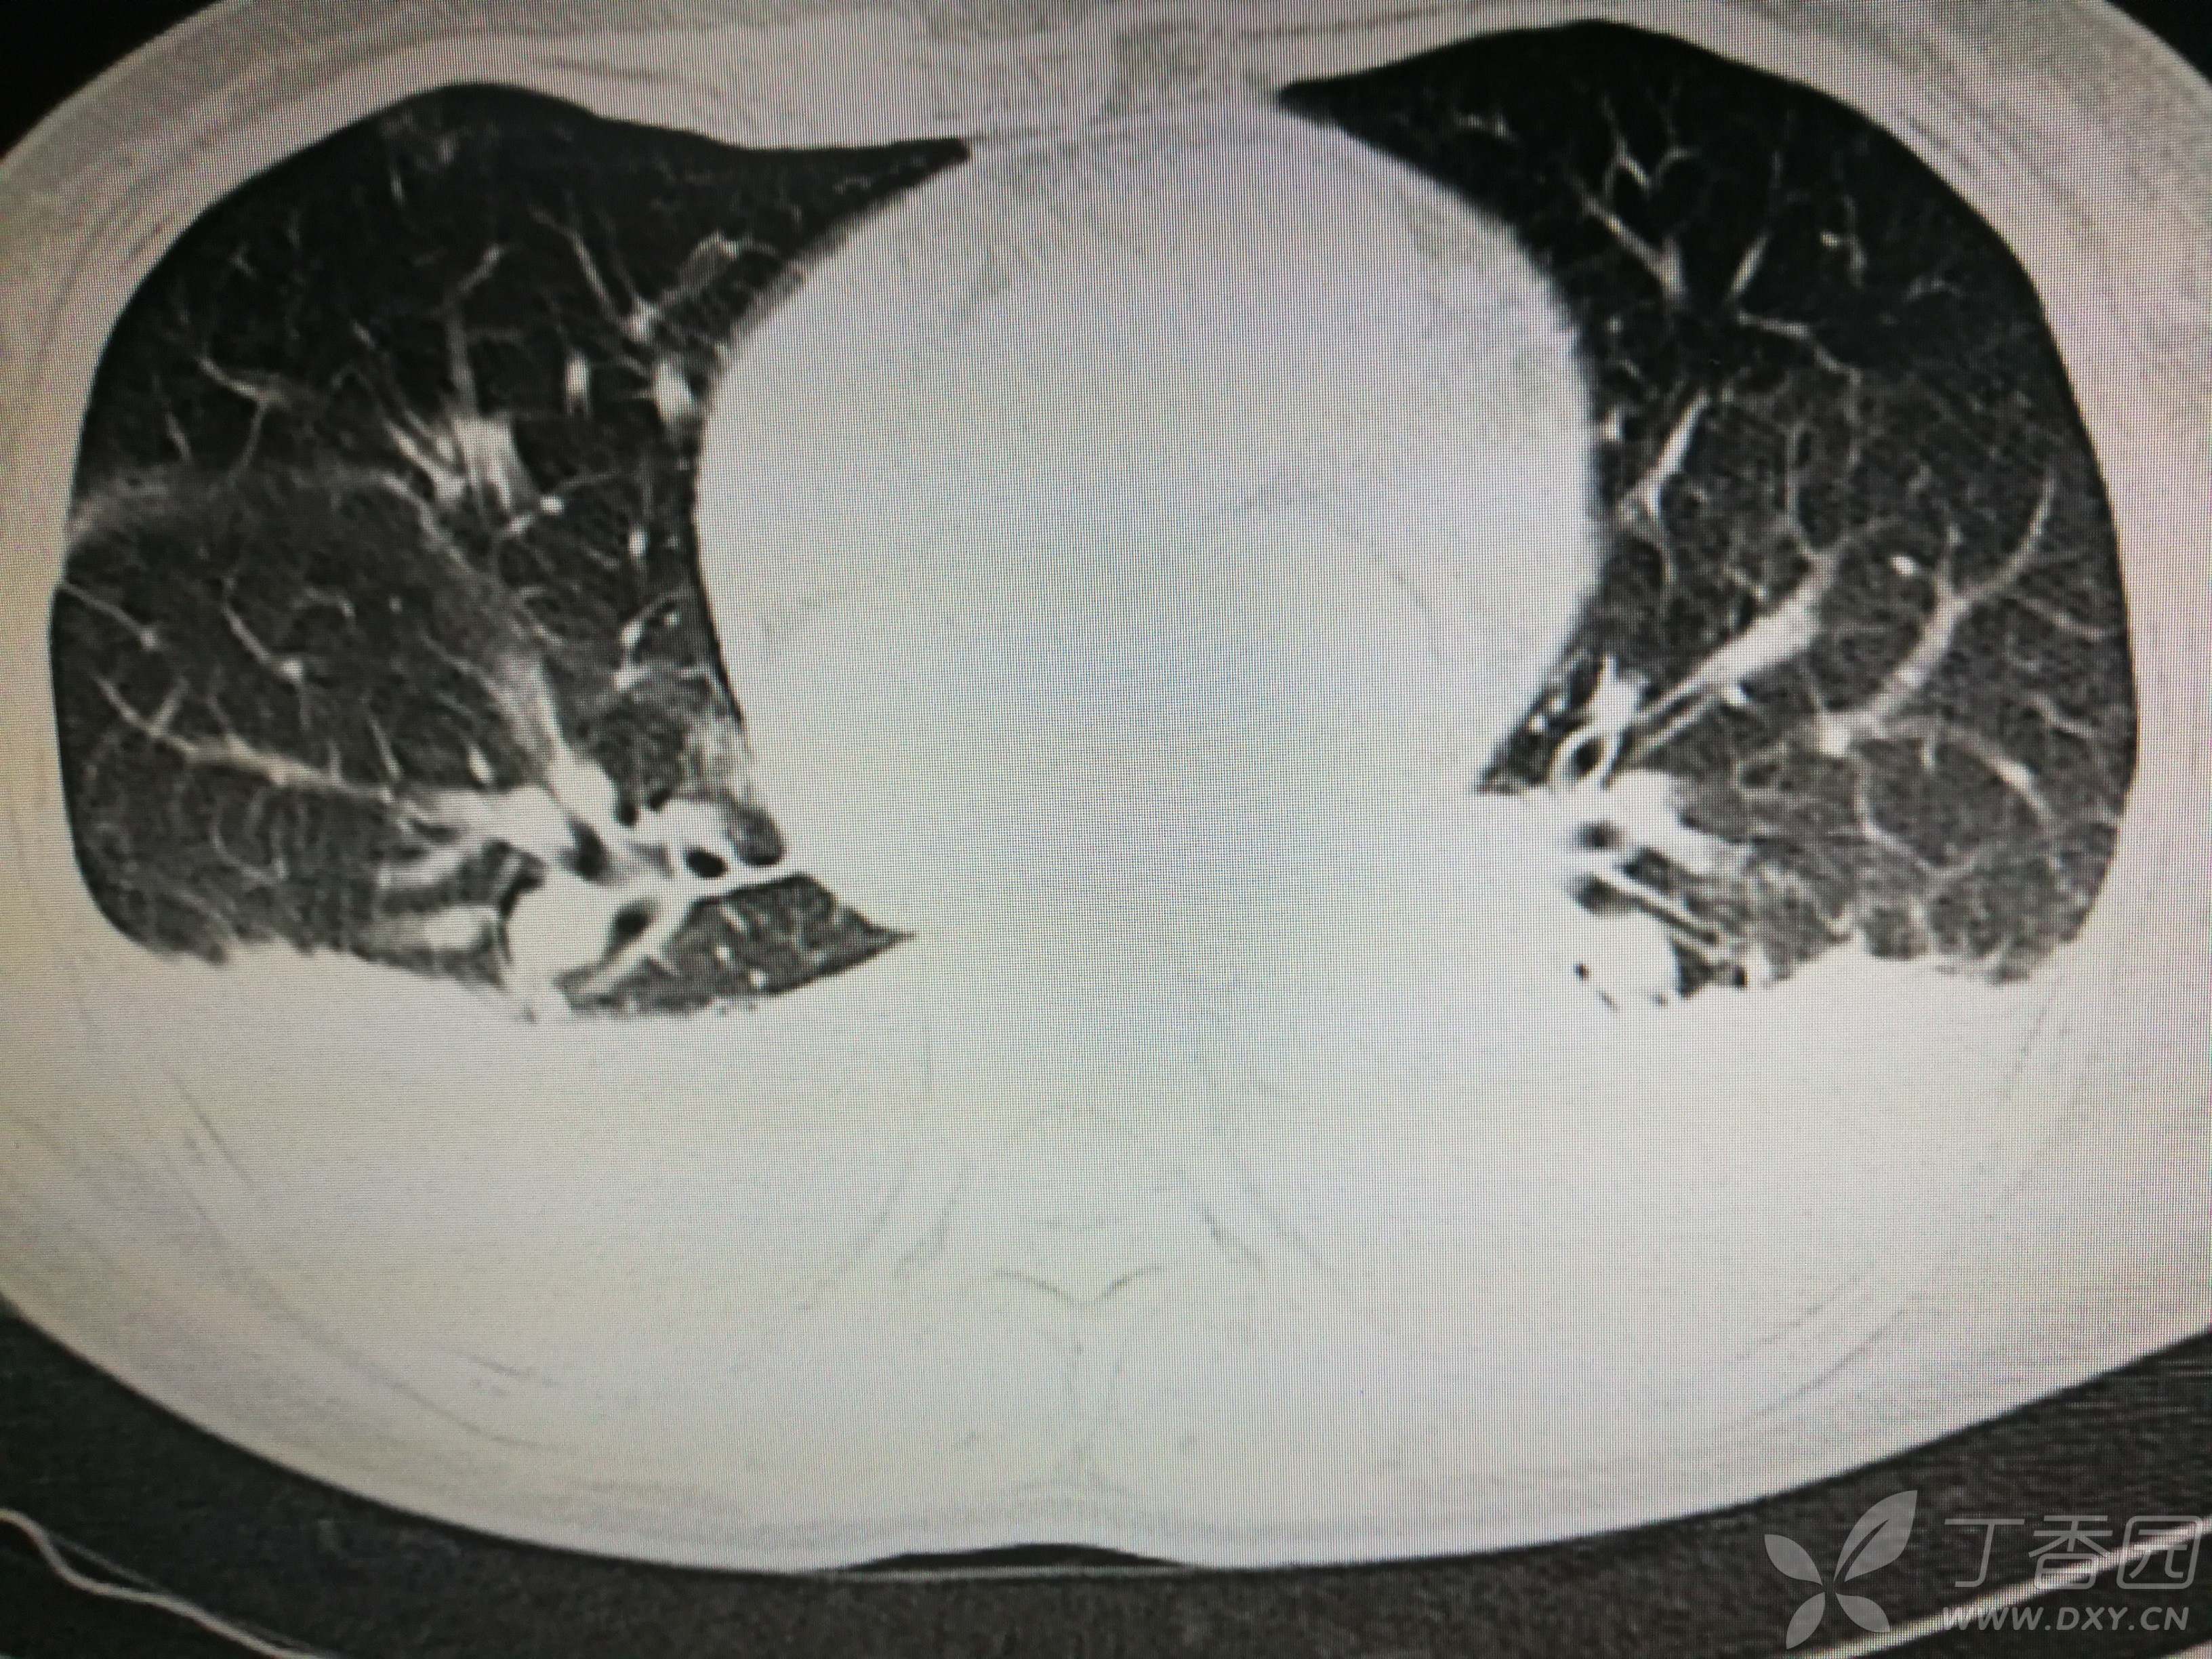

给予低分子肝素钙针抗凝、七叶皂苷钠针消肿及骨牵引固定等等治疗。入院后第四天行“左侧股骨下段骨折切开复位内固定术”(术前查双下肢彩超:双下肢深静脉血流通畅),手术顺利,术后予预防感染、预防血栓形成等治疗。术后患者无明显发热,生命体征平稳。术后第四天复查血常规:白细胞13.4×109/L,血红蛋白84g/L,血小板在正常范围。生化:白蛋白35.7g/L,余无明显异常。当天,患者开始出现轻度胸闷气急,可耐受。术后第五天患者胸闷气急加重,无胸痛,无背痛,无咯血,无意识障碍,无头晕头痛,无恶心呕吐等,急查凝血功能:纤维蛋白原降解产物12mg/L,D二聚体4000ug/L,余无明显异常。查动脉血气分析:pH7.52,氧分压62mmHg,二氧化碳分压30mmHg,碱剩余1.8mmol/L,乳酸1.0mm/L,血红蛋白86g/L。查胸部CT见下(先视频后图片):